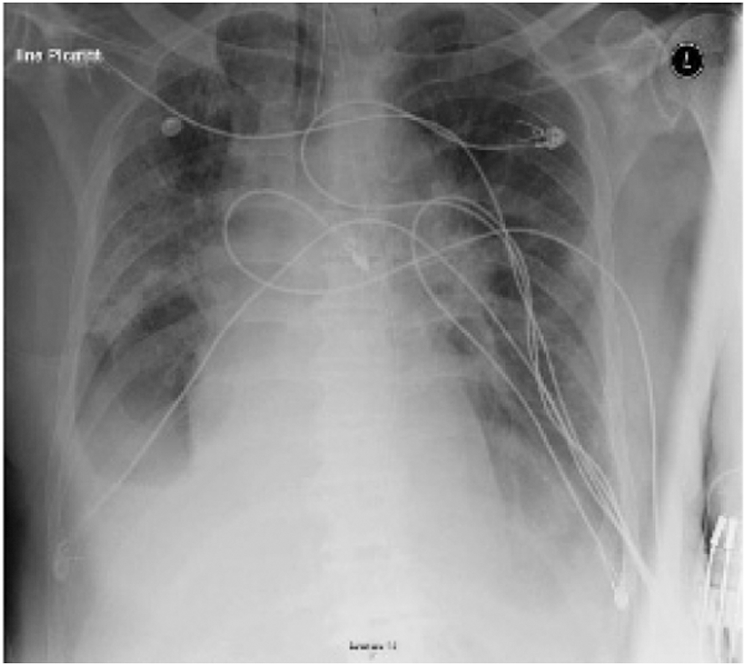

Fig. 7 illustrates a 74-year-old male patient of 6 or more days offset of symptoms with a past medical history of Parkinson disease, cardioembolic stroke, atrial fibrillation, chronic obstructive pulmonary disease (COPD) [16]. He admitted to the emergency with a complaint of cough and fever. The patient tacked a full check-up plus chest x-ray. The diagnosis was an exacerbation of COPD, and the patient was discharged home with an oral antibiotics. After 24 hours, the patient returned to the emergency, with worsening symptoms, counting altered mental status, fever headache, and cough. He admitted to the hospital for more check-up. Therefore, he was suspected for COVID-19 infection. The patient was isolated and repeated the chest X-ray. The new X-ray, Fig. 7, demonstrated a small right pleural effusion with bilateral ground glass opacities. The patient was then tested for COVID-19 and found to be positive. The patient developed respiratory failure and required intubation and was transferred to the ICU.

Figure 6: Chest X-ray displays multifocal airspace opacities with bilateral ground glass opacities of one case belong to Group C [16]